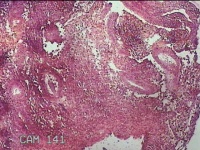

宫颈内容物

性别

女

年龄

29岁

临床诊断

异常子宫出血

一般病史

不规则阴道流血1个月余。

标本名称

大体所见

灰白暗红色不规则碎组织1.8x1.3x0.3cm一堆。

图2